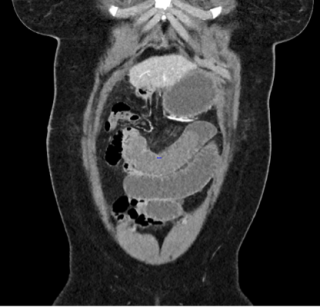

Case presentation

A 55-year-old overweight man presented with one week of right-sided abdominal pain with recent worsening despite outpatient medical therapy. He was hemodynamically stable but had right upper quadrant tenderness and localized guarding. Laboratory testing showed elevated C-reactive protein with a normal leukocyte count and normal liver biochemistry. CT demonstrated inflammatory fat stranding of the right greater omentum with a hyperdense rim, consistent with right-sided omental infarction (Figure 1). Because pain persisted despite conservative management, diagnostic laparoscopy was performed and confirmed ischemic omentum with hemorrhagic peritoneal fluid (Figure 2), and a normal gallbladder and appendix. Laparoscopic omentectomy was completed without complications. Histopathology confirmed omental infarction (Figure 3). The patient was discharged on postoperative day 1 and remained asymptomatic at 6-week follow-up.